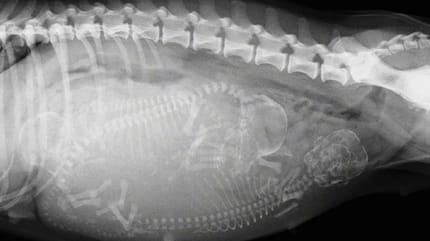

Castrar a tu perro o gato como prevención

Los datos analizados en esta ocasión vuelven a demostrar la necesidad de avanzar en la esterilización. Es decir, castrar a perros y gatos, sean machos o hembras, para evitar que la cifra de abandono animal continúe subiendo.